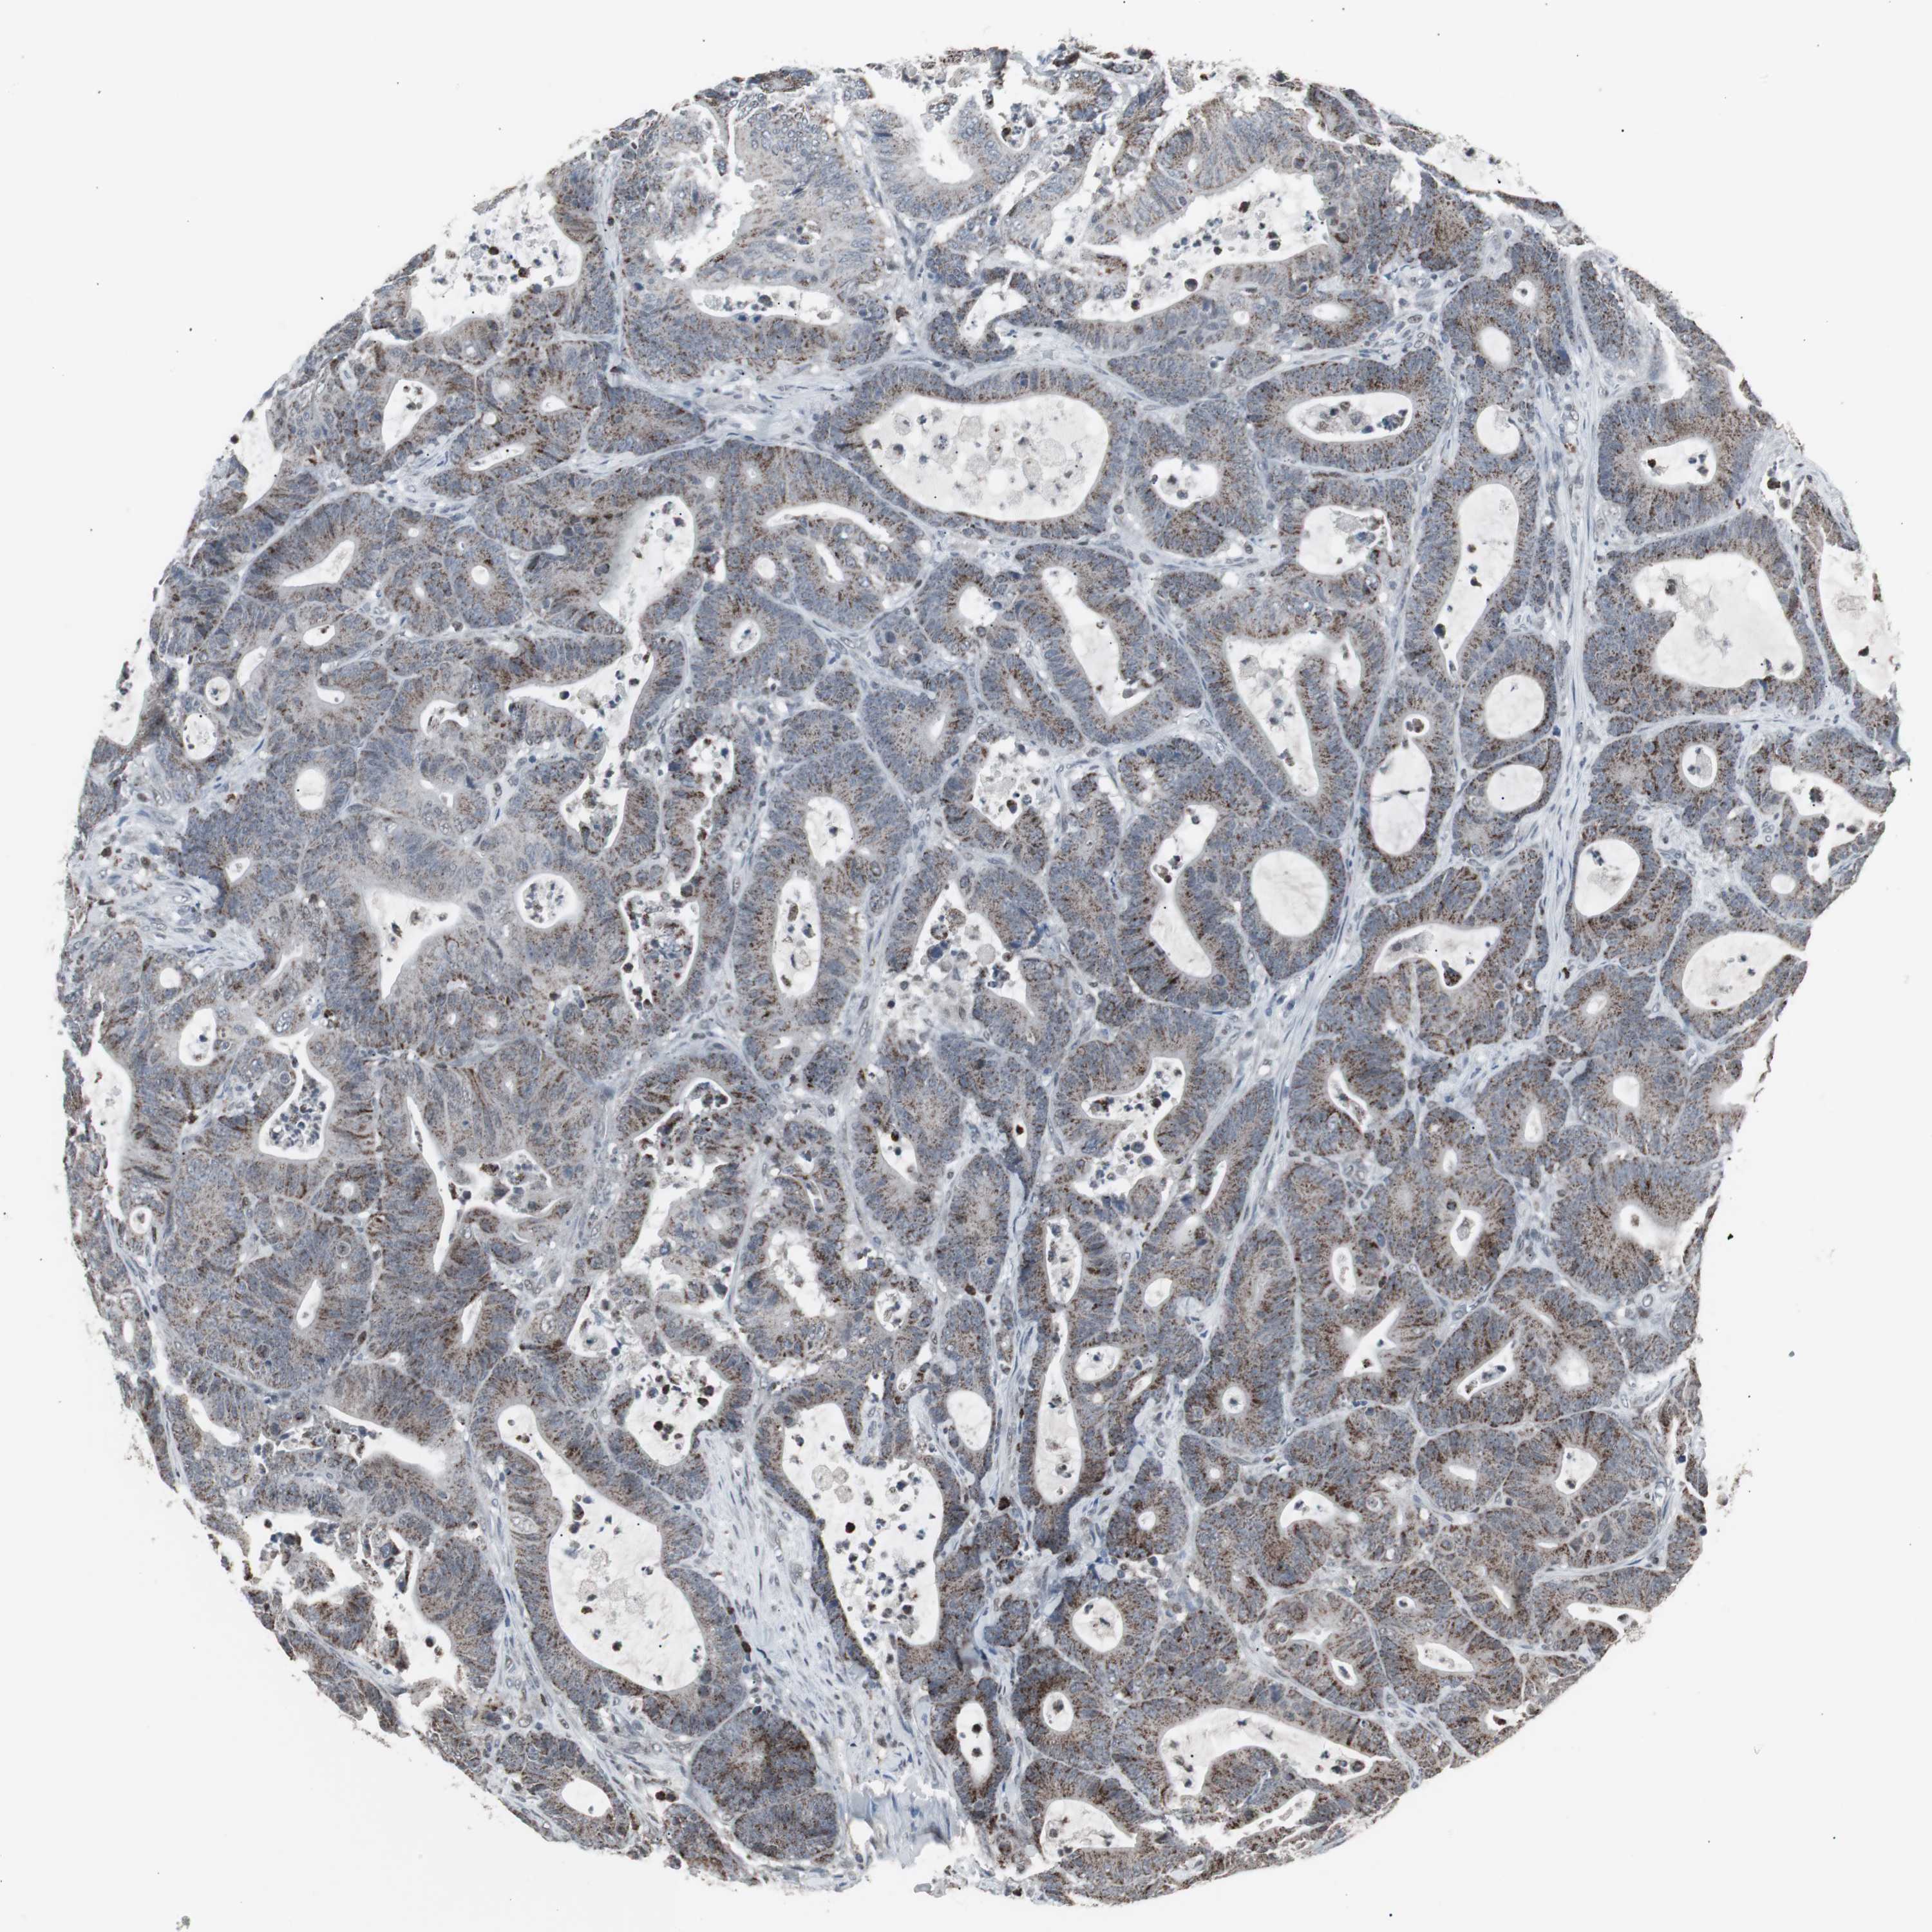

COLON ADENOCARCINOMA (VALIDATION) - Interactive survival scatter ploti

RXRA is not prognostic in Colon Adenocarcinoma (validation)

TCGA RNA samplesi

Average pTPM 28.2

Number of samples 486